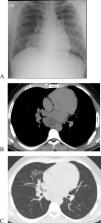

We report a case of a 25-year-old male with no relevant medical history or smoking habits who sought medical care for a subacute cough lasting four weeks. Clinical examination was unremarkable. Chest X-ray showed right mediastinal enlargement, and chest CT evidenced a 64 × 50 mm infracarinal mediastinal mass and a right middle lobe consolidation (Fig. 1A–C). Videobronchofibroscopy revealed small nodular lesions on the left main bronchus entrance and middle lobe bronchus narrowing due to a “cauliflower” lesion (Fig. 2A-B). Bronchial biopsies, endobronchial ultrasound, and transbronchial needle aspiration of station 7 lymph nodes were performed. Bronchial and lymph node samples showed solid to trabecular pattern neoplasia with keratin pearls and abrupt keratinization. Immunohistochemistry was positive for NUT protein (C52B1; 1:40; Cell Signaling Technology, Inc., USA), p40, p63, CK5, CK34B12 and CD56 (Fig. 2C–E), and negative for TTF-1, Napsin-A, synaptophysin, chromogranin and CD34. FISH and RT-PCR were not performed.